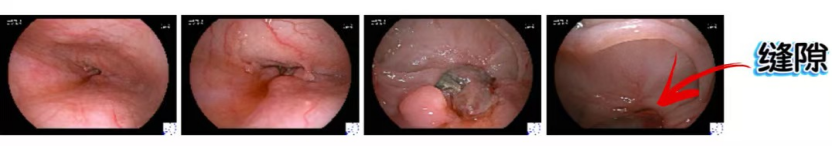

患者被查出距门齿30cm处食管存在瘢痕样变化与肿瘤组织共存的恶性狭窄,狭窄中央见不规整指状突起,质脆易出血,既往曾单纯在透视下尝试导丝突破未果。相马宁教授凭借丰富的临床经验和精湛的技术,在全身麻醉气管插管、内镜辅助透视下展开手术。

放置前:

放置后:

手术中,相马宁教授在内镜下找到缝隙,造影管引导至狭窄缝隙处,导丝突破狭窄,造影管跟随确认狭窄段约3cm余,且导丝顺利过贲门至胃内盘绕。随后留置导丝撤出内镜,在透视下沿导丝送入支架系统,精准地在临近贲门口侧释放支架。由于狭窄部较为坚硬,支架展开速度缓慢,撤离支架系统也面临困难,但相马宁教授借助内镜与透视的双重辅助,最终成功且安全地撤除支架系统。整个治疗过程中,患者生命体征平稳,术后顺利安返病房。